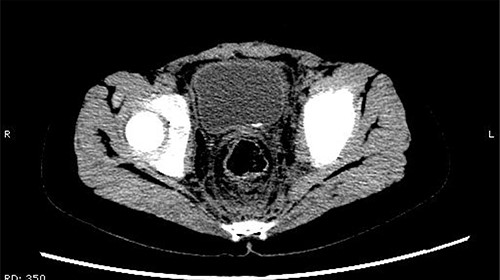

The patient was confined to bed, fasted and prescribed a daily intravenous infusion of cefazolin sodium pentahydrate, 2.0 g for 10 days. CT showed some irregular high-density shadows were present in the left renal pelvis (Fig. 1), and a small strip of high-density shadow was apparent in the bladder cavity (Fig. 2). Blood tests showed no abnormality in serum calcium concentration. Cefazolin sodium pentahydrate was discontinued immediately.

Some irregular high-density shadows was present in the left renal pelvis.